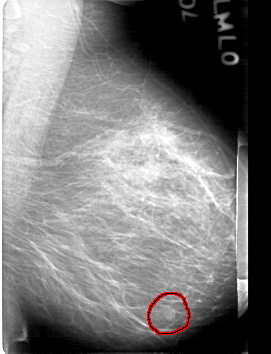

D_4086_1.RIGHT_MLO

FILE: D_4086_1.LEFT_MLO.OVERLAY

TOTAL_ABNORMALITIES 1

ABNORMALITY 1

LESION_TYPE MASS SHAPE OVAL MARGINS OBSCURED

ASSESSMENT 0

SUBTLETY 4

PATHOLOGY BENIGN

TOTAL_OUTLINES 1

BOUNDARY